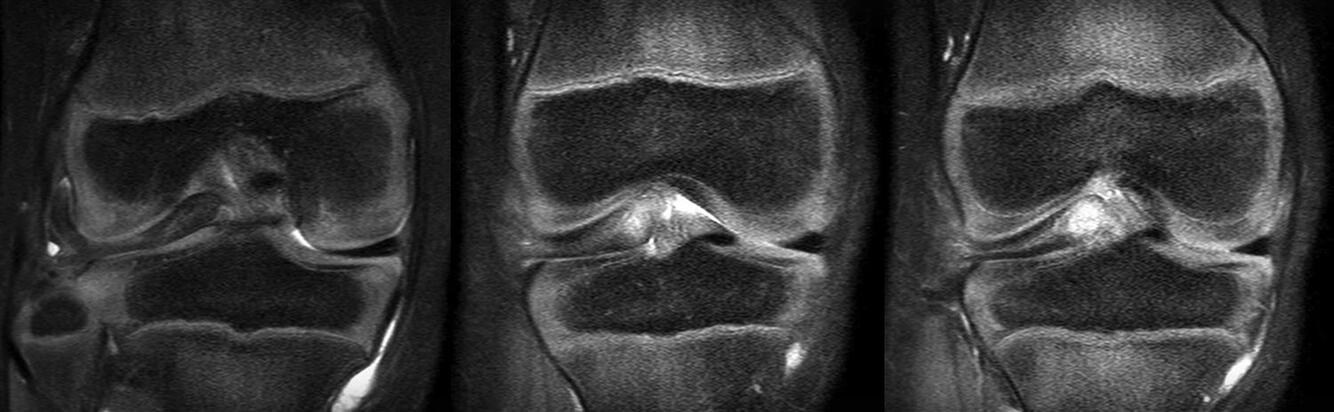

A 40-year-old man who is a manual laborer has had 3 years of worsening medial-sided left knee pain that has inhibited his ability to work. He reports undergoing a left subtotal medial menisectomy 10 years ago. He has been treated with nonsteroidal anti-inflammatory drugs and 2 different corticosteroids, with the most recent injection given 1 month ago. Each injection provided him with a few weeks of pain control. His medical history is unremarkable and he has smoked 20 cigarettes per day for the last 15 years. His body mass index (BMI) is 22. On examination, he has varus alignment of the involved leg and medial joint line tenderness and no lateral or patellofemoral pain. His knee range of motion is 3° shy of full extension to 130° of flexion. He has negative Lachman and posterior drawer test results. He demonstrates no lateral thrust with ambulation. What imaging study is most appropriate to determine treatment options for this patient? Based on his exam, what should be the next step in management after imaging?

This patient has a classic presentation of postmeniscectomy medial compartment arthritis. The appropriate diagnostic study is weight-bearing radiographs to confirm the diagnosis. An MRI scan will reveal medial compartment arthritis but will not provide information about alignment. A CT scan would be appropriate to detect an occult fracture; however, this condition is not suspected in this clinical scenario. Ultrasonography can provide information about fluid collection around the knee or a deep vein thrombosis; however, these conditions also are not suspected in this clinical scenario. Because the patient has a correctable deformity (gaps 3 mm with valgus stress), and his symptoms are localized to the involved compartment, a trial of a medial unloader brace is appropriate both diagnostically and therapeutically. If unloading the medial compartment resolves the patient's symptoms, he would be an excellent candidate for an osteotomy. An MRI scan may be obtained to evaluate ligamentous integrity or to evaluate degenerative involvement of the lateral and patellofemoral compartment for presurgical planning of an osteotomy; however, the integrity of the medial meniscus has no clinical importance in a patient with severe medial compartment arthritis. A repeat corticosteroid injection is not indicated within 1 month of his last injection, and referral to pain management is not appropriate with other options available to help this patient. A VPHTO is the appropriate intervention considering the patient's young age, high-functional occupation, examination, radiographic findings, and response to medial unloader bracing. A revision knee arthroscopy would be appropriate for a recurrent medial meniscus tear, but not appropriate in a patient with severe medial compartment arthritis. The patient's young age and high functional requirements are contraindications to TKA. The presence of severe arthritis is a contraindication to medial meniscus transplant. The patient is a candidate for a VPHTO. The technical options include a medial opening-wedge or a lateral closing-wedge osteotomy. Both techniques have advantages and disadvantages; however, a medial opening-wedge osteotomy is contraindicated in a smoker because of concern for nonunion. As a result, current smoking history is the only factor listed that would influence the technique used. The history of prior arthroscopy has no relevance in the decision about which type of osteotomy is appropriate. Normal BMI is between 18.5 and 24.9, so this patient's BMI is considered normal and would not affect the surgical technique (if this patient were obese, a lateral closing-wedge osteotomy would be considered, but this is controversial). His age of 40 years is an indication for HTO but does not influence technique.